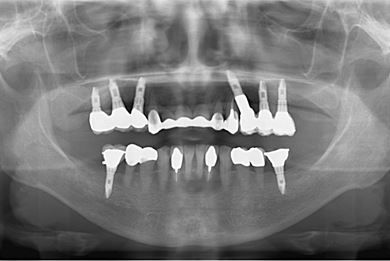

インプラントの症例写真 IMPLANT

| 治療内容 | インプラント8本(抜歯即日スピードインプラント、サイナスリフト)、ハイブリッドセラミック8本 | ||||||||||||||||||||||||||||||||

| 総治療費 | 3,495,050円 | ||||||||||||||||||||||||||||||||

| 治療期間 | 1年0ヶ月 |